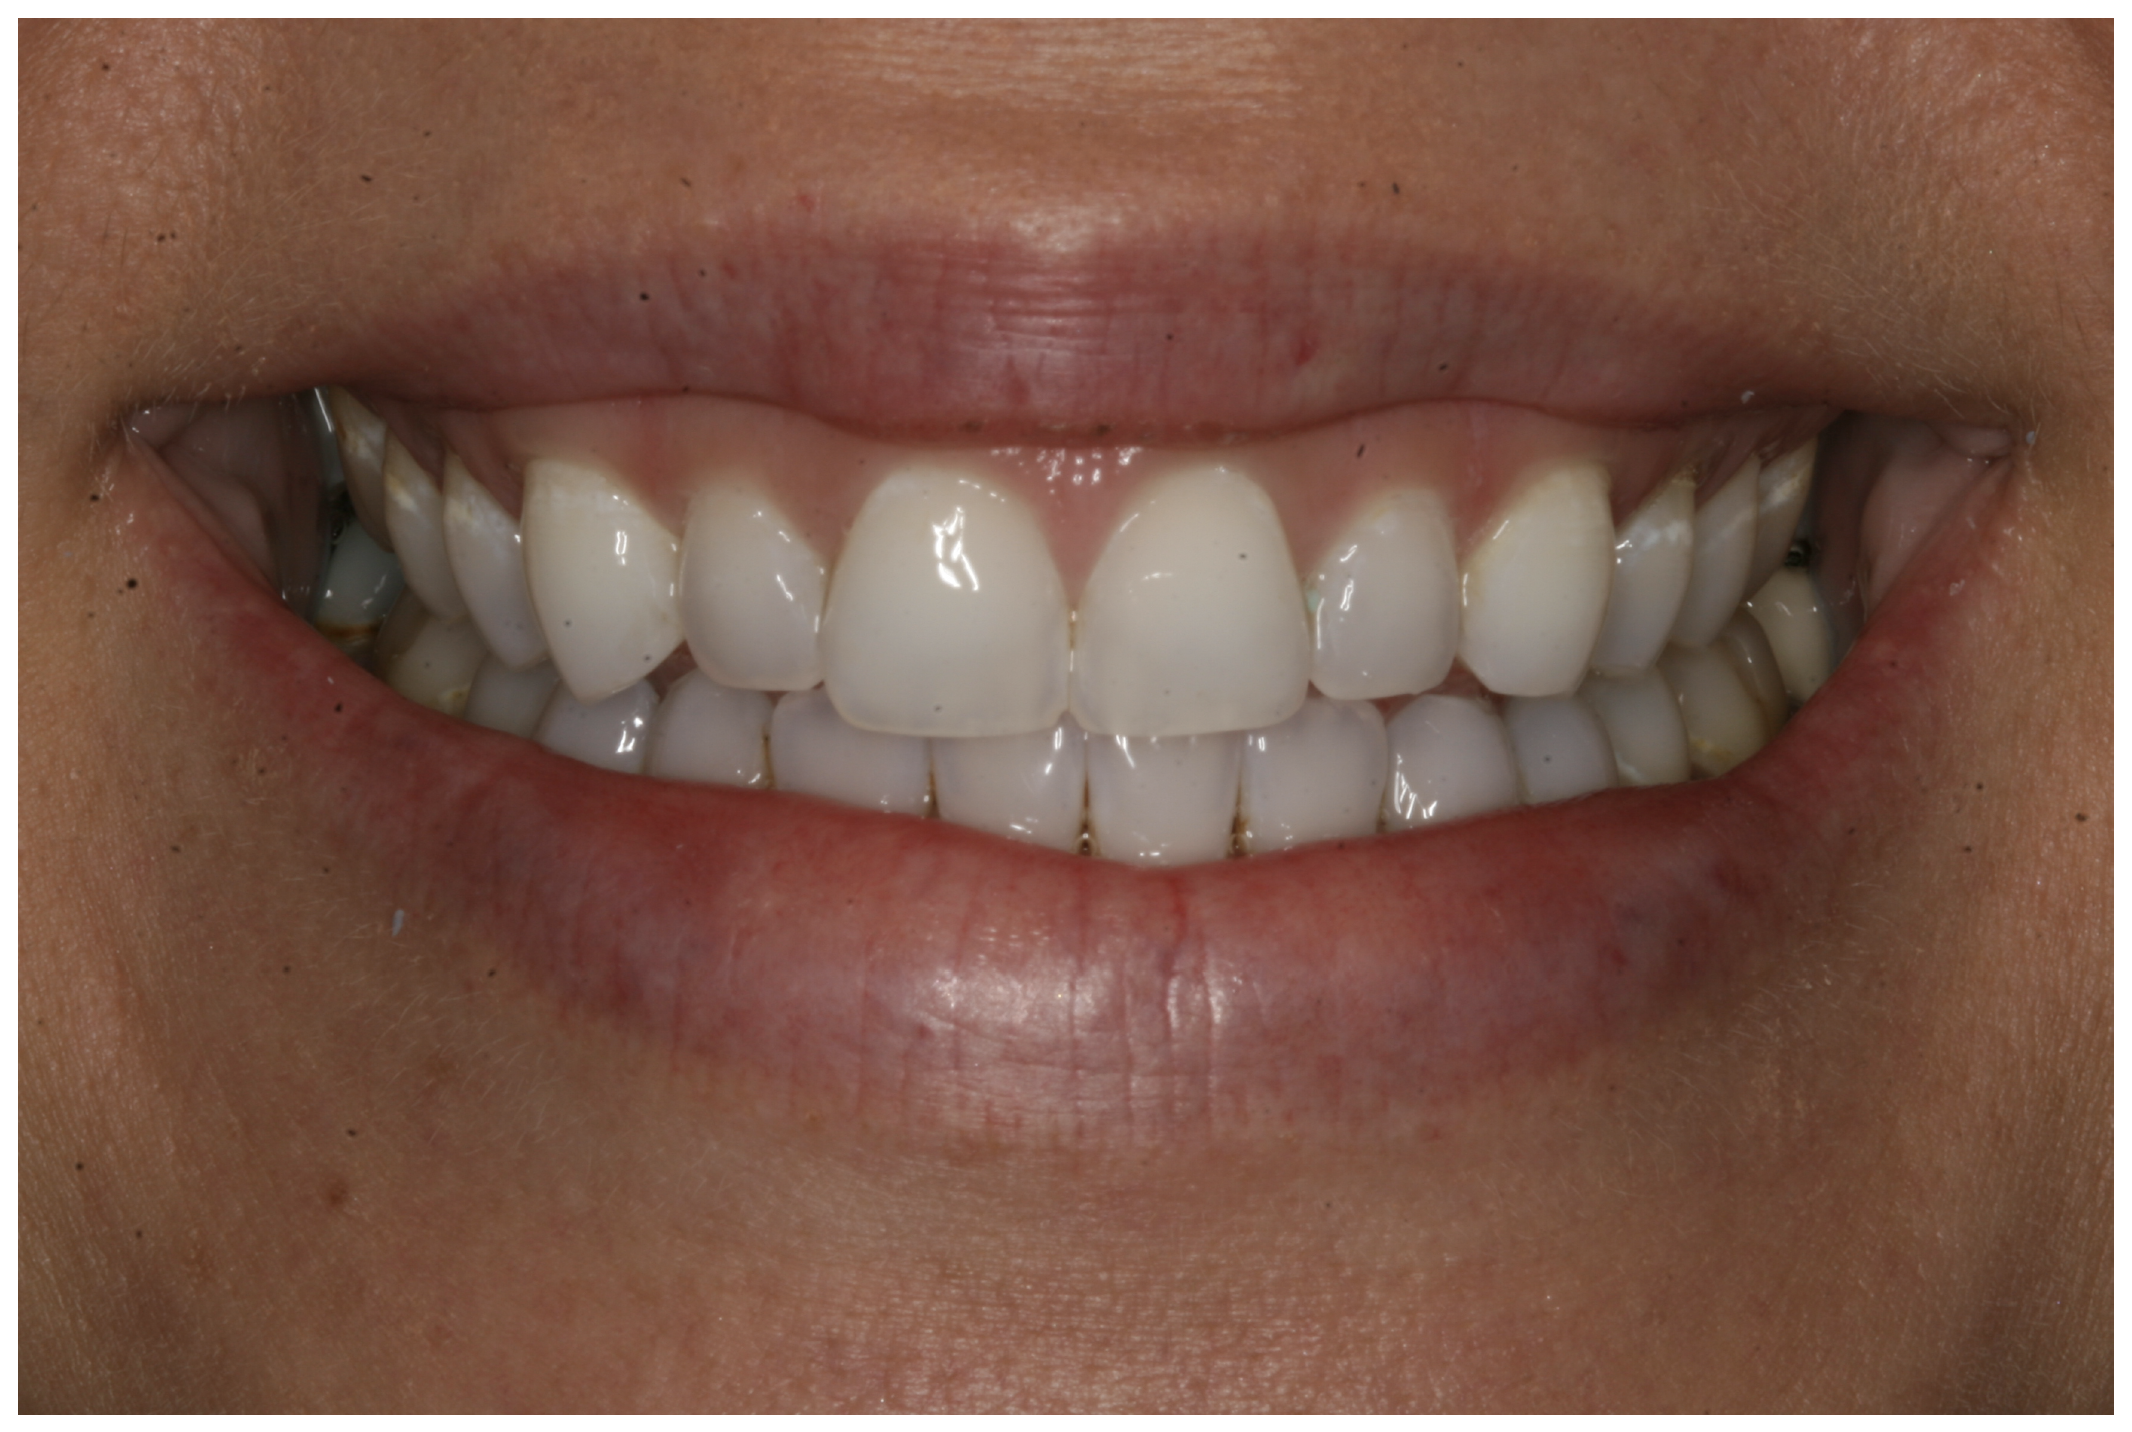

For the case in Figure 9 through Figure 11, the patent presented for an initial consultation with bonding completed on teeth Nos. 7 through 10 a few years prior with a chief complaint of not liking the way the resin bonding looked and how it was wearing. Up to this point, the bonding had repeatedly chipped and been repaired three times already. The patient's canines also exhibited signs of incised wear and flattening, which she did not like. Based on the patient's goals for her smile and her financial budget, she elected to have porcelain veneers completed on teeth Nos. 6 through 11. The total esthetics of the case design were somewhat limited given that the patient's esthetic zone included her posterior teeth and mandibular anterior teeth. Therefore, the color and characteristics of the veneers had to match her existing dentition closely.